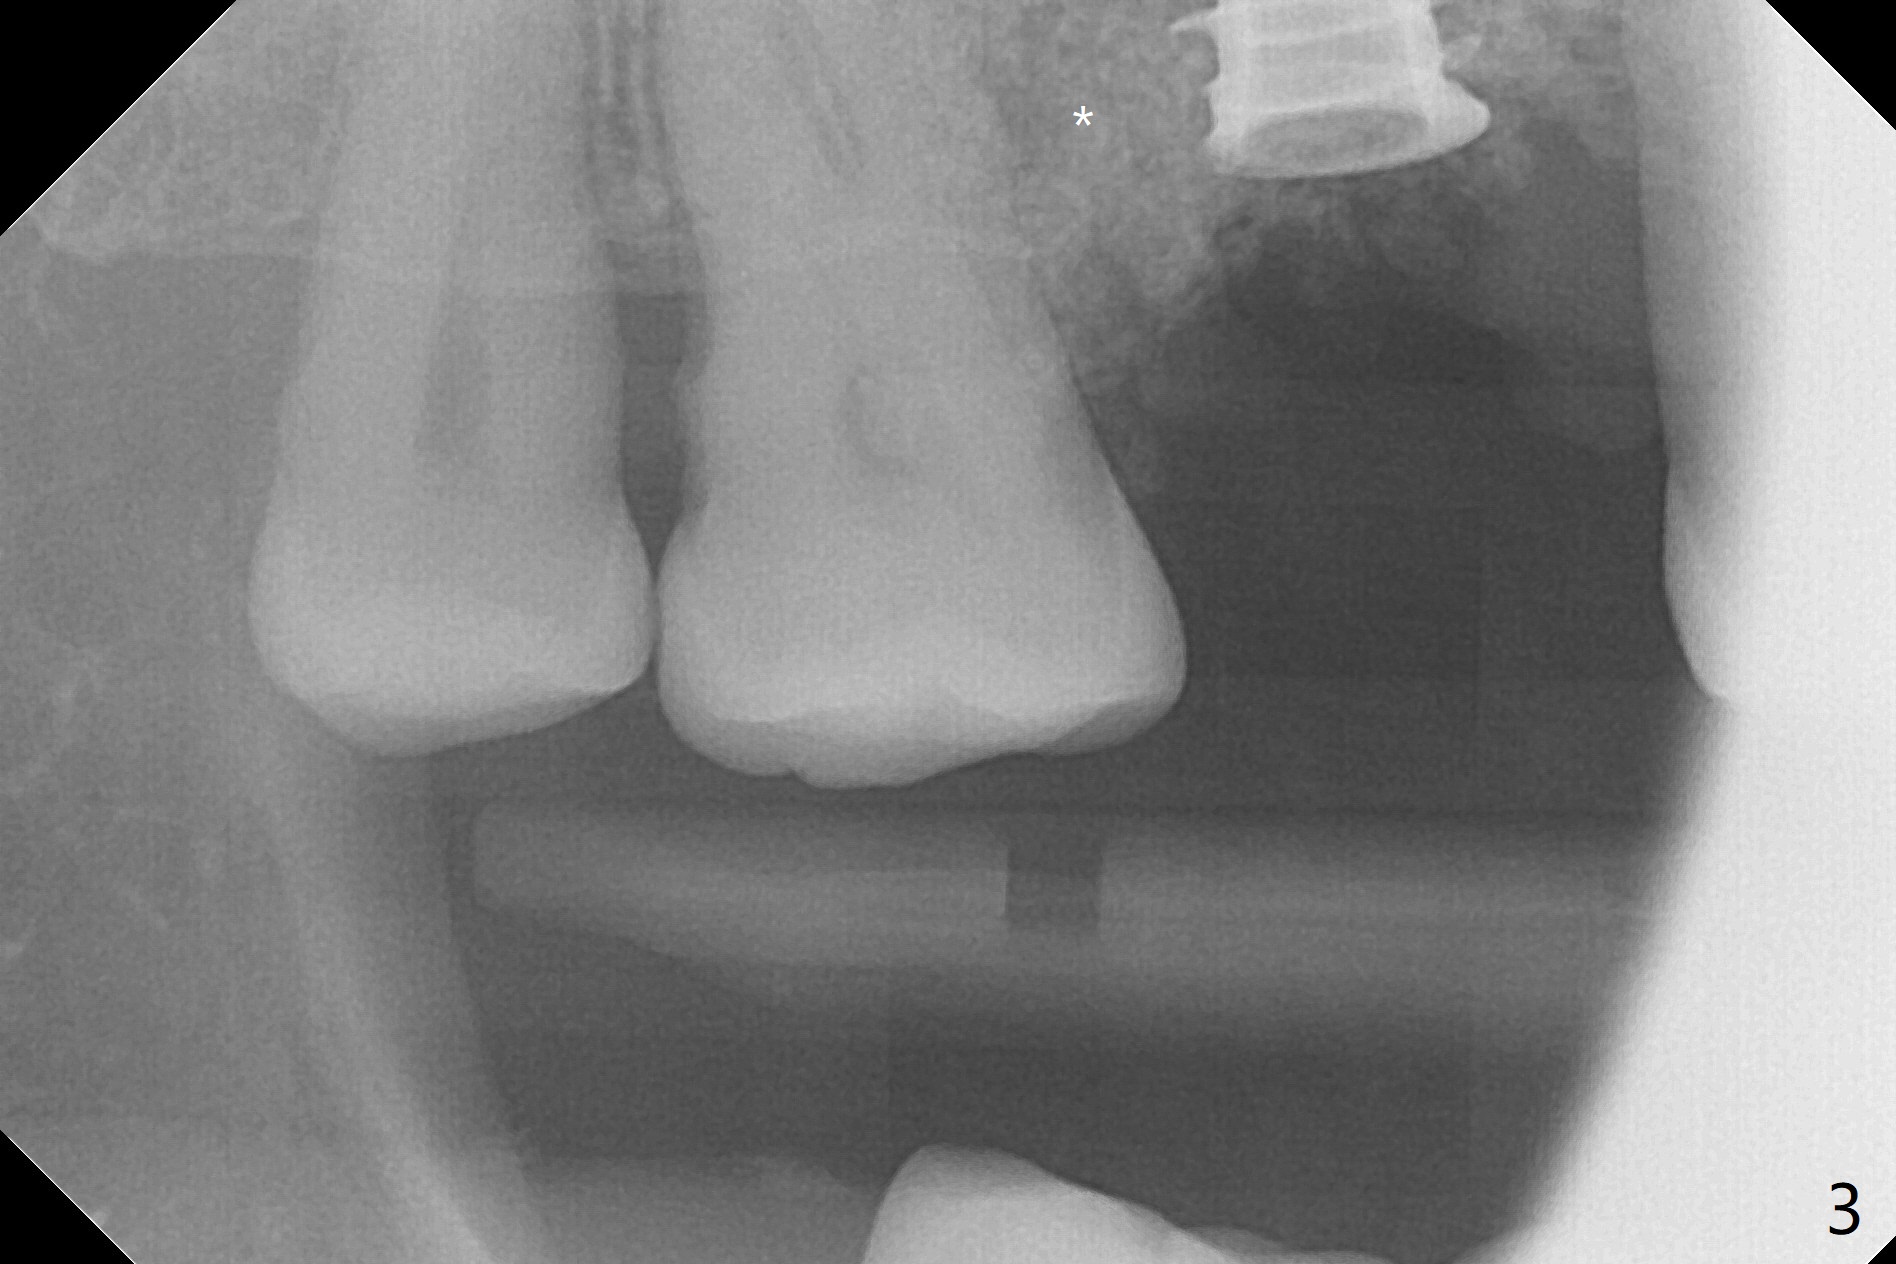

After extraction and debridement, osteotomy is initiated in the mesiobuccal socket free hand. Since the remaining bone is ~ 2 mm, the sinus floor is perforated suddenly. Fortunately the sinus membrane is not, as related to its thickening (similar to water ballooning, without symptom). Use 2-3.5 mm drills to enlarge the bony perforation (mainly lateral movement), followed by pushing bone graft upstairs with a curette (Fig.1 *); insert a 4x9 mm dummy implant (Fig.1) to determine the length of the final implant (Fig.2,3). A drawback of this case is the low torque (<20 Ncm), considering the thin bone. Following deeper implant placement, a 5.2x6(2) mm temporary abutment is placed for an immediate provisional to keep large amount of bone graft in place (Fig.3 *). There is no pain 1 week postop, while the immediate provisional remains stable partially because of the temporary abutment (Fig.4 ^). Four months postop, the temporary crown is loose. After removal of the temp and the temp abutment, gingival cuff is erythematous. A 6x4 mm healing abutment is placed. The bone graft (Fig.3 *) appears to have attached to the root of the neighboring tooth and the implant threads 7 months post op (COVID 19, Fig.5 arrowheads)). The bone graft appears to continue to merge with the neighboring root, bone and implant 10 months postop (2.5 months post cementation, Fig.6). The bone graft in the sinus seems to collapse and condense 10 months postop (Fig.7 *).